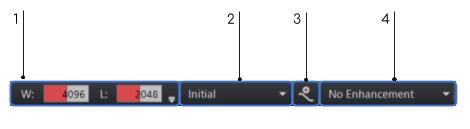

Window/Level

The PACS supports preset settings for window width and center. Preset settings allow you to group together one or more settings to a specific function, and then apply those settings all at once by selecting the tag from a list. In the case of preset window and level, you can create modality specific window/level pairs, and apply them to a selected image by selecting them from the list. The preset list of window and level values provide a list of all saved window/level settings for a specific modality type. The preset window/level list appears in the window/level toolbar. The list of preset values is in the pull-down menu. A few default values exist in the preset window/level list.

Window Level Values

Preset window/level menu

Save current W/L

Enhancement Filter Presets